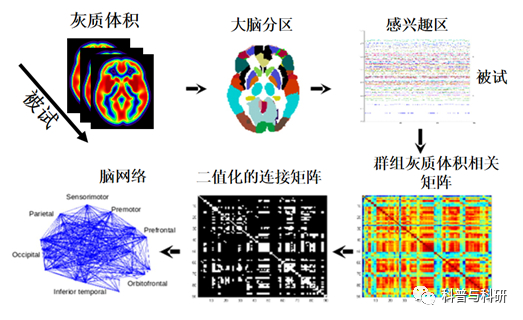

VBM讲解、操作 |

1、脑结构分析及VBM分析原理介绍 2、VBM分析流程、操作步骤详解(VBM8) 3、VBM分析流程、操作步骤详解(CAT12) 4、统计、画图 |

结构协变理论介绍 |

1、结构协变网络原理介绍 2、结构协变脑网络数据预处理 3、结构协变脑网络构建 4、 |

基于多模态磁共振影像的人脑连接组学介绍 |

1、人脑连接组学介绍 2、结构网络、功能网络构建介绍 3、基于GRETNA 的静息态 fMRI 数据预处理实操及注意事项 |

基于静息态 fMRI 的 脑功能网络构建 |

1、基于GRETNA 静态功能网络构建 2、脑网络拓扑属性介绍 3、脑网络拓扑属性计算 |